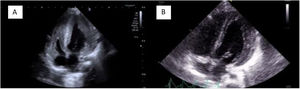

Lactante con diagnóstico de enfermedad de Pompe (glucogenosis tipo II), diagnosticada a los 7 meses tras episodio de insuficiencia respiratoria severa con hipotonía. La ecocardiografía inicial mostró una miocardiopatía hipertrófica no obstructiva: septo interventricular en telediástole (SIVtd) 14mm Z-score +5,48, pared posterior VI (PPVItd) 16mm Z-score +7,71, diámetro diastólico VI (DDVI) 18mm Z-score −3,61 y fracción de eyección VI (FEVI) al 50% (figs. 1A, 2A y 3A).

Se inició tratamiento enzimático sustitutivo con avalglucosidasa-alfa (Nexviadyme®), observándose a los 2 meses una clara mejoría estructural y funcional: ventrículo izquierdo no dilatado ni hipertrófico (SIVtd 6mm Z-score +1,6, PPVItd 7mm Z-score +3,42, DDVI 28mm Z-score +0,81) y FEVI aumentada al 63% (figs. 1B, 2B y 3B).